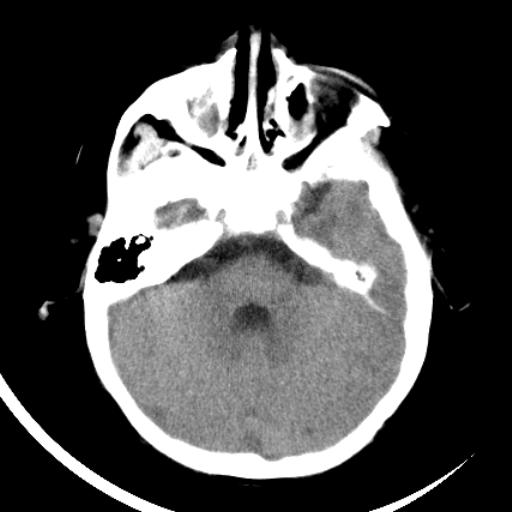

双侧脑室前后角周围白质片状低密度影,双侧侧脑室旁、双顶叶皮层及皮层下多个小原点状钙化灶,不除外torch感染。右顶叶脑回似乎较对侧大,建议mri检查以除外脑发育异常。

考虑:1、巨脑回畸形(皮质明显增厚+脑回明显增宽+白质减少)。

2、torch综合征(室管膜下钙化+白质内及皮髓质交界处多发钙化)。

结节性硬化并无脑回畸形,左侧枕顶叶不排除血管畸形。